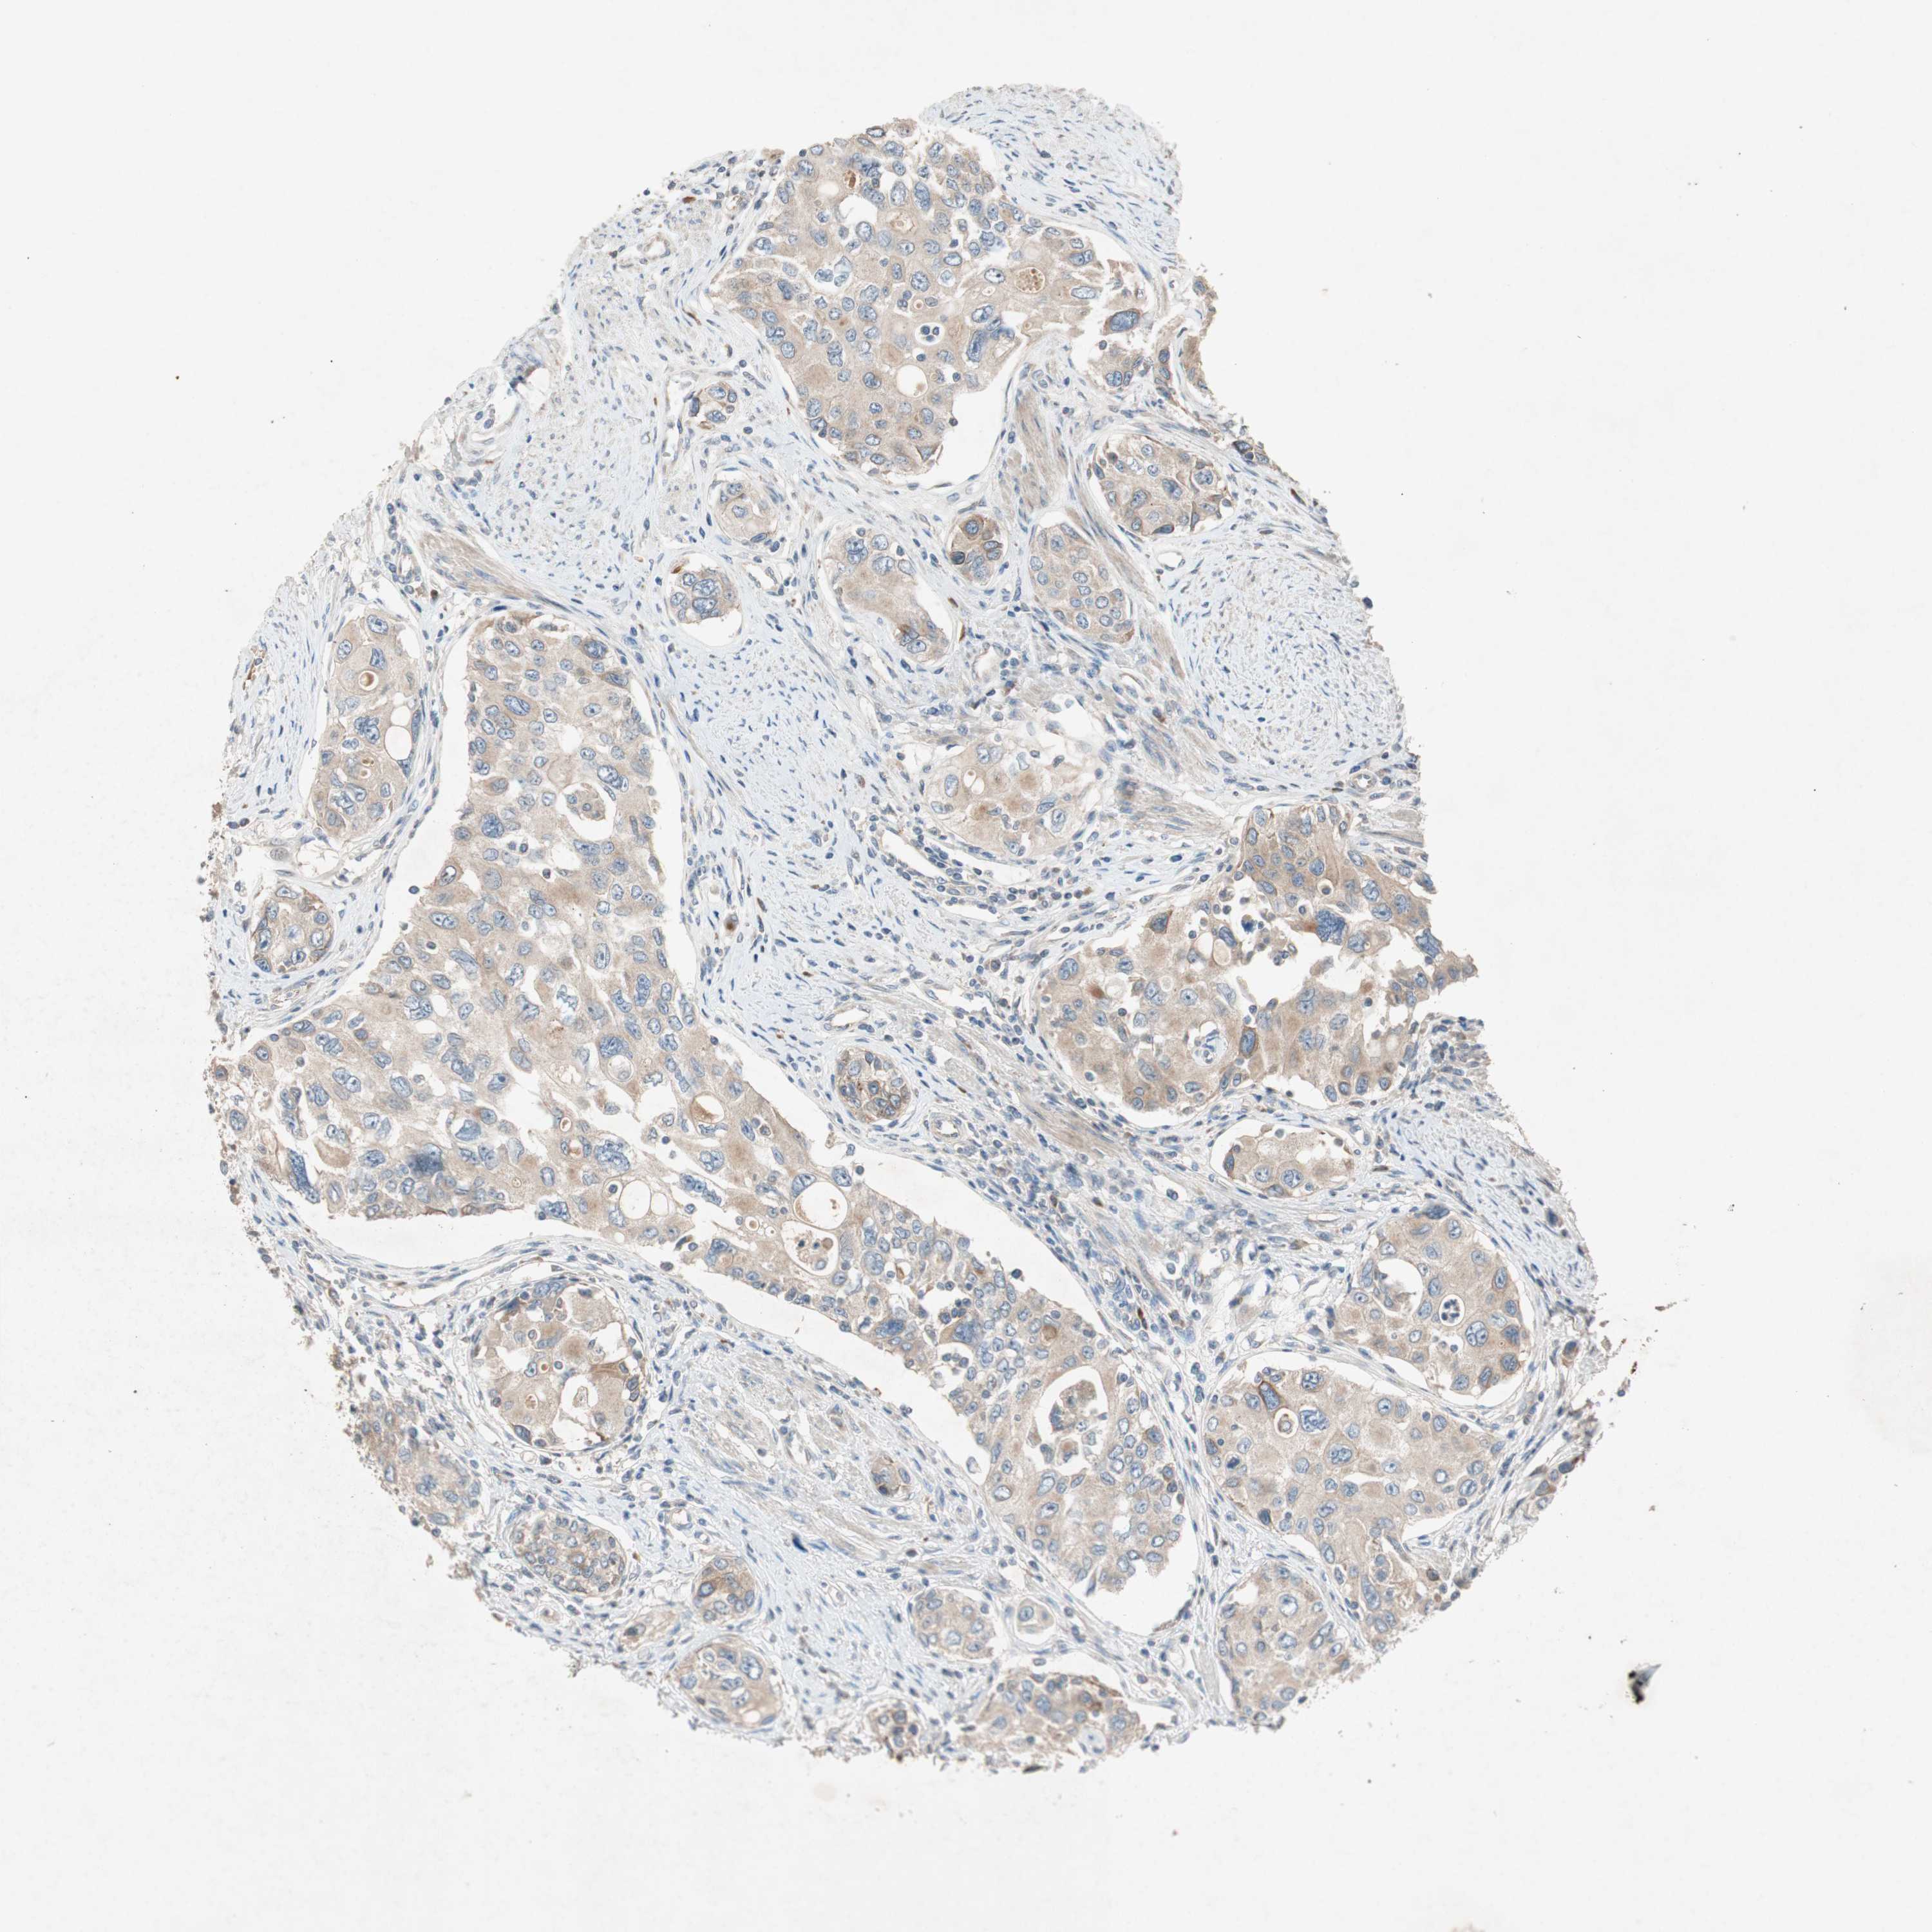

UROTHELIAL CANCER - Protein expressioni

A mouse-over function shows sample information and annotation data. Click on an image to view it in a full screen mode. Samples can be filtered based on level of antibody staining by selecting one or several of the following categories: high, medium, low and not detected. The assay and annotation is described here.

Antibody stainingi

Antibody staining in the annotated cell types in the current human tissue is reported as not detected, low, medium, or high, based on conventional immunohistochemistry profiling in selected tissues. This score is based on the combination of the staining intensity and fraction of stained cells.

Each image is clickable and will lead to virtual microscopy that enables deeper exploration of all samples and also displays staining intensity scores, fraction scores and subcellular localization as well as patient and tissue information for each sample.

Antibody HPA003187

Staining

High

Medium

Low

Not detected

Intensity

Strong

Moderate

Weak

Negative

Quantity

>75%

75%-25%

<25%

None

Location

Nuclear

Cytoplasmic/membranous

Cytoplasmic/membranous,nuclear

Urothelial carcinoma, Low grade

Urothelial carcinoma, High grade